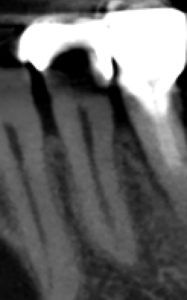

術後にPA, CBCTを撮影した。

問題はないだろう。

根尖病変はないので最終補綴OKである。